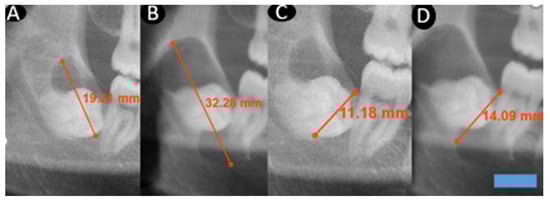

This retrospective study evaluated the radiographic records of patients who presented to the Department of Oral and Maxillofacial Surgery at Dicle University Faculty of Dentistry between 2020 and 2024, underwent biopsy, and received a histopathological diagnosis of dentigerous cysts. Among 187 patients with a definitive post-treatment diagnosis, 12 had previously been scheduled for surgical intervention but failed to attend their appointments (Table 1). Only histopathologically confirmed dentigerous cysts were included in the study. Consequently, radiolucent lesions that could mimic dentigerous cysts were excluded, which inherently limited the scope for comparative analysis. These individuals later returned to the clinic after varying intervals of time. Prior to treatment, new panoramic radiographs were obtained, and repeat biopsies reconfirmed the diagnosis of dentigerous cysts. As patients were informed about the potential risk of neoplastic transformation of these cysts, they were encouraged not to delay treatment, and due to the small number of individuals who postponed their procedures, the sample was limited to 12 patients. To be included in the study, lesions had to remain untreated solely for patient-related reasons, and follow-up panoramic radiographs suitable for comparison had to be available at least six weeks after the initial imaging. In our study, among the included radiographs, the earliest follow-up visit occurred 8 months after the initial radiograph, whereas the latest was recorded 108 months after the initial radiograph. For these 12 patients, the initial panoramic radiographs were compared with follow-up images obtained several months later, focusing specifically on lesions involving the same impacted teeth and corresponding anatomical regions (Figure 1 and Figure 2). Dimensional changes in the cysts over time were measured, and monthly growth rates were subjected to statistical analysis. Only high-quality panoramic radiographs that were clear, properly positioned, and minimally affected by patient-related factors such as movement or improper alignment were included. All images were acquired using devices of the same make, model, and system (Planmeca ProMax 2D (Planmeca Oy, Helsinki, Finland) with DentAssist software (version 4.1.200)), ensuring imaging standardization. The original radiographs were subsequently converted to DICOM format to enable precise digital analysis, and all radiographic measurements were calibrated using the built-in calibration system integrated into the imaging device. In this study, dentigerous cyst lesions were identified on panoramic radiographs, and their dimensions were measured to evaluate changes over time. Because lesion growth rates may differ according to anatomical location, only dentigerous cysts associated with impacted mandibular third molars were included. For each patient, the largest anteroposterior (A–P) and inferosuperior (I–S) dimensions of the cyst were recorded on two panoramic radiographs obtained at different time points. Each dimension was measured twice on every radiograph, and the mean value of the two measurements was used for comparison. All measurements were performed by the same investigator, with each measurement repeated twice to enhance consistency and minimize intra-observer variability. The time intervals between radiographs were standardized and expressed in months for statistical analysis. The monthly growth rate represents a mathematical standardization obtained by dividing the dimensional difference between two radiographs by the elapsed time; it is not intended to directly observe short-term radiological changes.

Figure 2. This figure demonstrates changes in cyst dimensions based on calibrated linear measurements obtained from panoramic radiographs at baseline and at long-term follow-up. The calibrated measurements highlight progressive enlargement over time and provide visual corroboration for the calculated growth rates derived from radiographic length assessments. A blue scale bar with a length of 10 mm and a height of 3 mm was added in the lower right corner of the image. (A): I–S first measurement. (B): I–S second measurement after 36 months. (C): A–P first measurement. (D): A–P second measurement after 36 months.